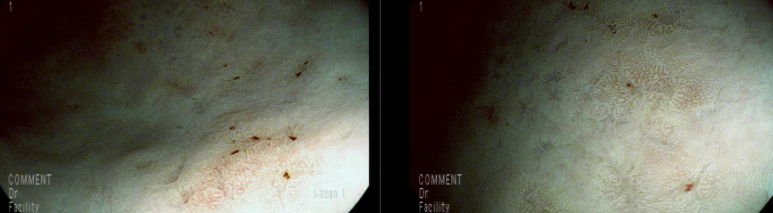

최근 음주를 많이 해서인지 발적, 미란성 변화 있으나 헬리코박터에 의한 만성 표재성 위염 소견은 의심되지 않음

장상피 화생 소견 있으며 조직검사상 일치함

; 요소호기검사 내시경 소견상 헬리코박터 제균되었을 확인함